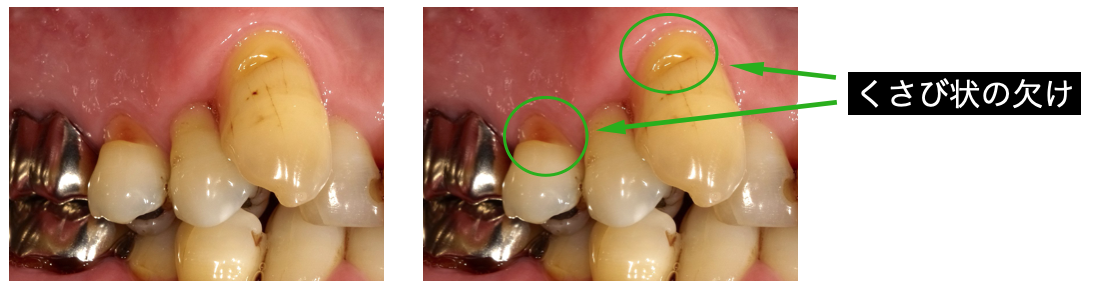

③噛み合わせに問題があったり、歯軋りや食いしばりの影響。

噛み合わせに問題があったり、歯軋りや食いしばりがあると、歯と歯茎の境目の歯質がくさび状に欠けてしまったり、冷たいものに過敏に反応してしまうことがあります。

ナイトガードによる力のコントロールや、欠損部の修復、しみ止め処置で改善する場合があります。